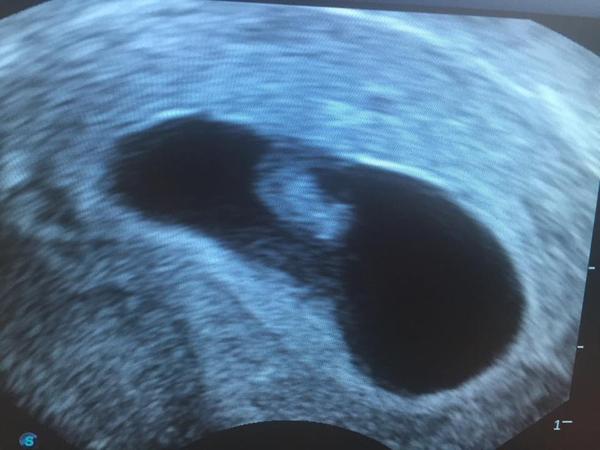

@ivetkavysocina mockrat dekuju a podle uktrazvuku jsem 7+5 tt dneska 🙂

@chupavogel gratulace 🙂 my jsme taky dopadli dobře, foto na mém profilu :D 😀

@chupavogel také moc gratuluji. Jsem ve stejné situaci a k doktoru jdu 4.8. Chtěla jsem se zeptat, obdržela jste již těhotenskou průkazku? Fazolka je krásná, těším se na tu naší 🙂